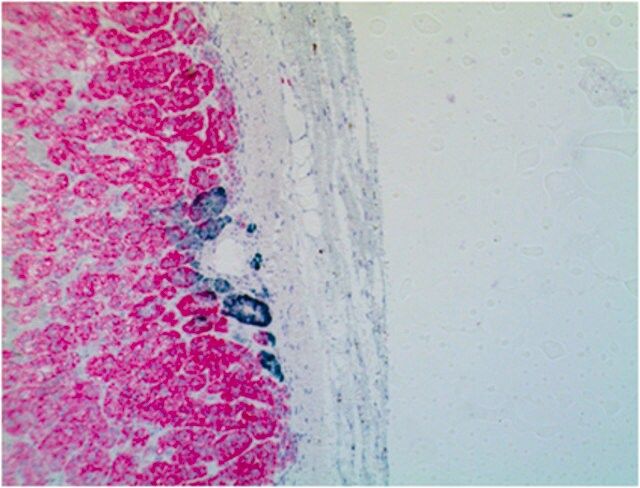

Anti-Amyloid beta A4 protein, clone 2E9 Antibody, Cat. No. MABN2295, is a highly specific rat monoclonal antibody that targets Amyloid beta A4 protein and has been tested in Immunofluorescence, Immunoprecipitation, and Western Blotting.

Immunofluorescence Analysis: A representative lot detected Amyloid beta A4 protein in Immunofluorescence applications (Willem, M., et. al. (2015). Nature. 526(7573):443-7).